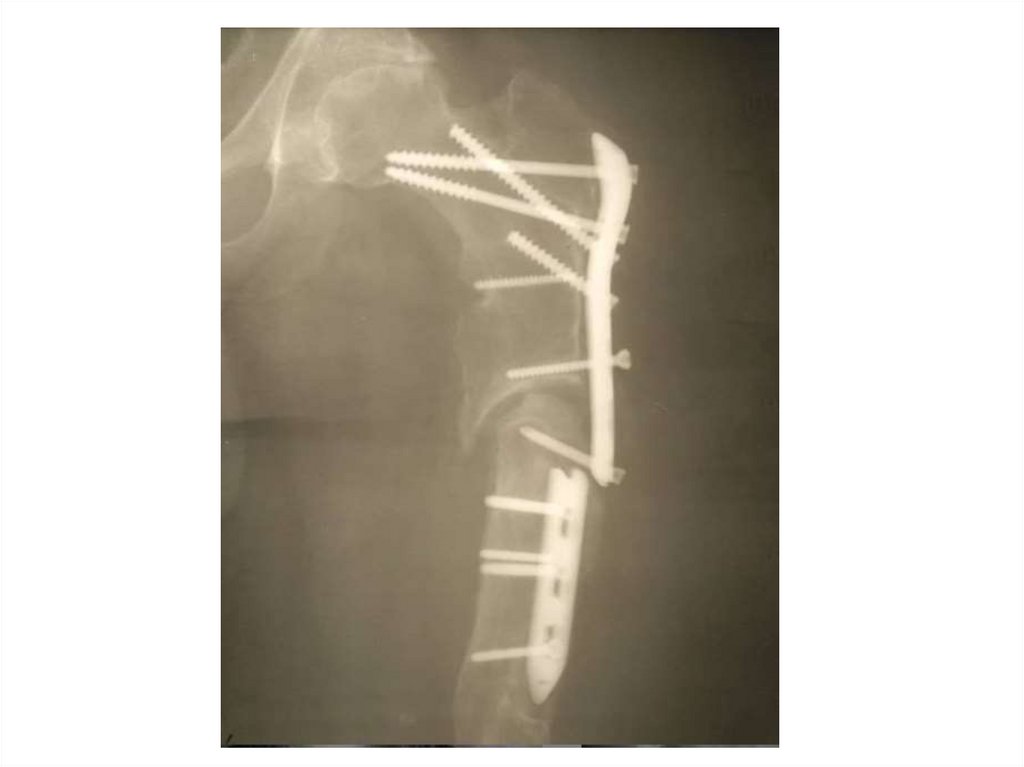

Назовите

• Вид исследования

• Область исследования

• Патологию